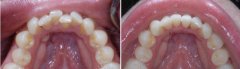

牙齿不齐怎么矫正?

看到明星一口整齐靓丽的牙齿,是否羡慕不已。随着现代医疗技术的进步,牙齿...【详细】